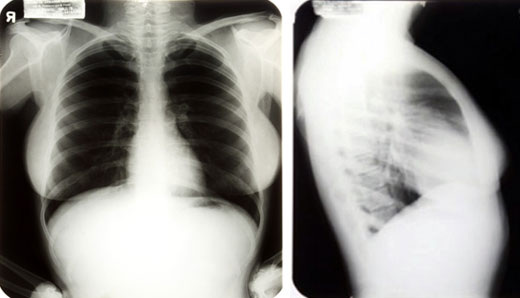

A las reveladoras notas escritas por el médico Michael Gurdin, supuestamente encargado de llevar a cabo la operación quirúrgica en 1950, se suman varias pruebas de rayos X realizadas el 7 de junio de 1962, dos meses antes del fallecimiento de la artista, en las que se pueden apreciar desde diferentes ángulos los huesos faciales de Marilyn, sus conductos nasales y su paladar.

Radiografías de Marilyn Monroe, bajo el nombre de Marilyn DiMaggio, sacadas por un joven médico en 1954.